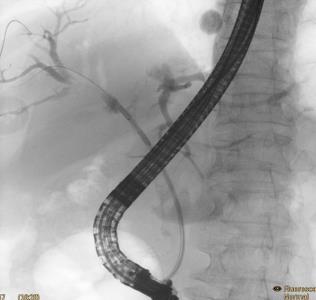

• 内镜射频消融术与光动力疗法治疗不可切除肝外胆管癌远期疗效的对比研究

摘要:目的 比较内镜射频消融术(RFA)与光动力疗法(PDT)联合胆道支架置入治疗不可切除肝外胆管癌的远期疗效。方法 回顾性分析2018年2月-2023年2月于该院接受内镜RFA或PDT治疗的胆管癌患者的临床资料,根据手术方法不同,将患者分为RFA组(n = 32,行内镜RFA联合胆道支架置入)和PDT组(n = 21,行内镜PDT联合胆道支架置入)。比较两组患者治疗次数、支架通畅期、总体生存期和并发症发生率,并分析影响患者生存期的危险因素。结果 RFA组与PDT组总体生存期分别为14.0(95%CI:11.8~16.2)和18.0(95%CI:15.4~20.6)个月,支架中位通畅期分别为4.0(95%CI:2.7~5.3)和3.5(95%CI:2.3~4.7)个月,差异均无统计学意义(P > 0.05);多因素Cox回归分析显示,内镜下RFA或PDT治疗次数的HR^ = 2.417,≥ 2次是影响总体生存期的保护性因素(P = 0.018),而TNM分期的HR^ = 0.300,Ⅲ期至Ⅳ期是影响总体生存期的危险性因素(P = 0.002);两组患者临床成功率均为100.00%;两组患者并发症总发生率[28.13%(9/32)和23.81%(5/21)]比较,差异无统计学意义(P > 0.05)。结论 内镜RFA与PDT联合胆道支架置入,治疗不可切除肝外胆管癌的远期疗效相似。内镜RFA或PDT序贯治疗 ≥ 2次,能够有效地延长患者的总体生存期。